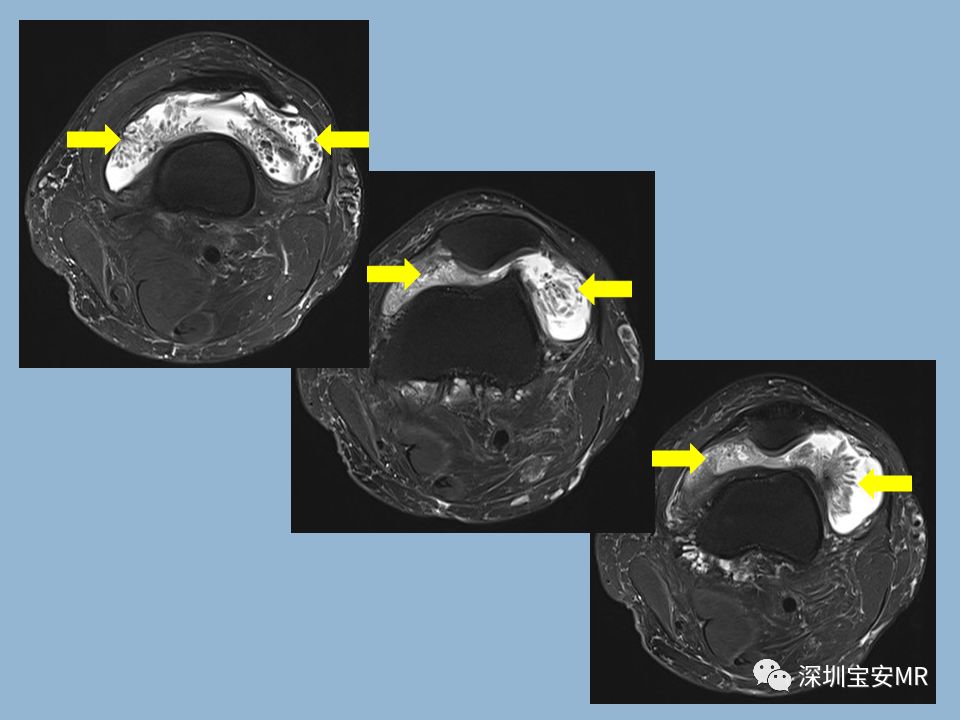

左膝矢状位、轴位、冠状位FS-T2WI:髌上囊可见树枝状、海草样低信号(黄箭),与皮下脂肪信号一致。髌上囊见大量液体信号。